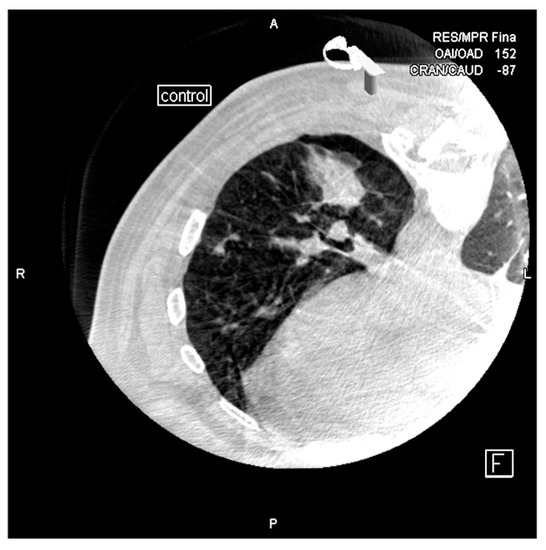

Cone-Beam CT-Guided Lung Biopsies: Results in 94 Patients

2. Materials and Methods